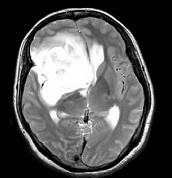

问题 女,32岁,头痛1年,复视4个月,请根据所提供图像,选择最可能的诊断()

选项 A.(右额颞)胶质母细胞瘤 B.(右额颞)多形性黄色星形细胞瘤 C.(右额颞)混合性胶质瘤(星形细胞和少突细胞) D.(右额颞)毛细胞型星形细胞瘤 E.(右额颞)室管膜下巨细胞星形细胞瘤

答案 C